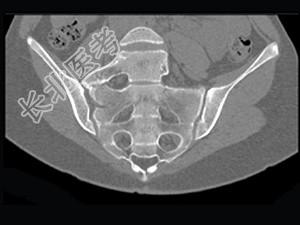

- 单项选择题男,35岁, 下腰部痛,L4-5棘突旁有明显压痛, 结合图像,最可能的诊断是 ( )

C、腰椎骶化

D、骶椎腰化